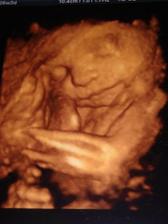

Tak dnes sme s budúcim tatinkom boli v slávnom Gennete a obaja sme odtiaĺ odchádzali s nadšením,pán docent bol skvleý,veĺký profesionál a odborník a hlavne nás ubezpečil,že malý je v poriadku a už teraz je to poriadny chlapisko 🙂

°°°°6.3.tak nás pustili domkov na priepustku,musíme sa ukázať 13.3.na kontrolu,sice nám zistili kvasinky,ale dali nám vagin.lieky na týždeň,tak verím,že piatok 13teho bude šťastný 🙂,inak na kontrolnom uzv sme videli,že hematom je už polovičný,čo je úžasné,pani doktorka mi prcka zase zmerala a ukázala orgány,keď sa dostala ku stehennej kosti a močovému mechúru,tak sme zistili,že máme nestydu 🙂,pani dr.sa smiala,že už chápe,prečo tak rozťahuje nožičky,ukazuje nám totiž hrdo,na čo je pyšný 🙂 °°°°budeme mať CHLAPČEKA 🙂°°°°